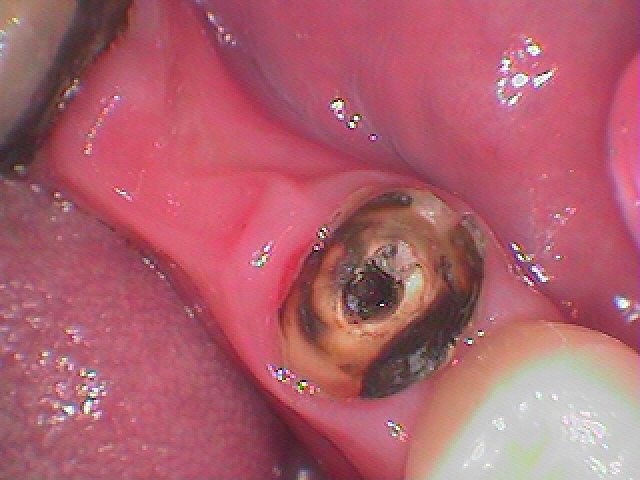

中は虫歯になっていました

被せを外していくと中は大きく虫歯になっていました